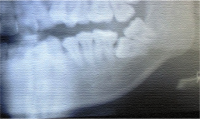

下顎8番の水平埋伏はしばしば見かけますが、図に示したような7番の水平埋伏もまれにあります。このようなケースの治療について情報交換を行いたいと思います。